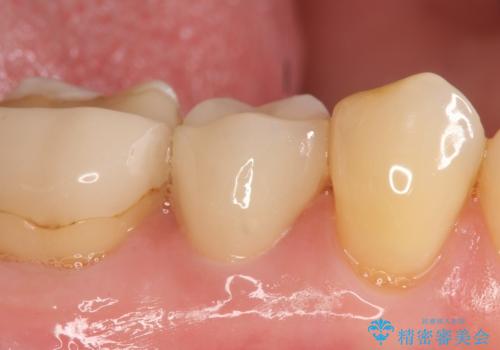

- 右下の銀歯が気になるといらっしゃった方の症例です。

右下6番目の銀歯を除去後、セラミックインレーによる修復を行いました。